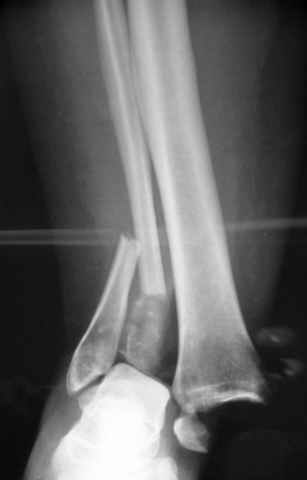

Re: ANKLE FRACTURE

Alexander Chelnokov 12 Сентябрь 2004, 15:11

Я вот все в толк не возьму смысл отдельной фиксации малоберцовой кости пластинкой, если все равно будет аппарат с фиксацией стопы, т.е. возможностью провести спицы в пятку, таран, наружную лодыжку и еще черт-те куда. Остеосинтез пластинкой выглядит логичным в случае, когда наружная фиксация планируется как временная. Но тут-то аппарат будет окончательным фиксатором.

Еще, кстати, о фиксации лодыжки, если уж непременно хочется ее отдельно стабилизировать - при таком характере перелома замечательно должен сработать предложенный проф. Лазаревым с соратниками способ фиксации напряженной V-образной спицей. Опять же, открытая репозиция не нужна, мы делаем непрямую репозицию именно аппаратом. В приложении пример, там перелом малоберцовой куда менее поперечный, чем в данном случае, но все равно получилось закрыто без пластинки.

I can't realize why plate fibula separately if anyway external fixator including the foot is planned, i.e. one may insert wires to the talus, calcaneus, lateral malleolus and anywhere else. Plating looks reasonable if only temporary ex-fix is planned, but in the case it will be definitive.

A propos fibular fixation if one is eager to stabilize it separately. In the fracture pattern a way of closed fixation by V-shaped stressed wire (advanced by colleagues from Moscow, prof. Lazarev A.F. et al.) must be excellent. We use indirect closed reduction by the external fixator. Example attached, that fibular fracture is even more suitable for plating but the wire did the job.